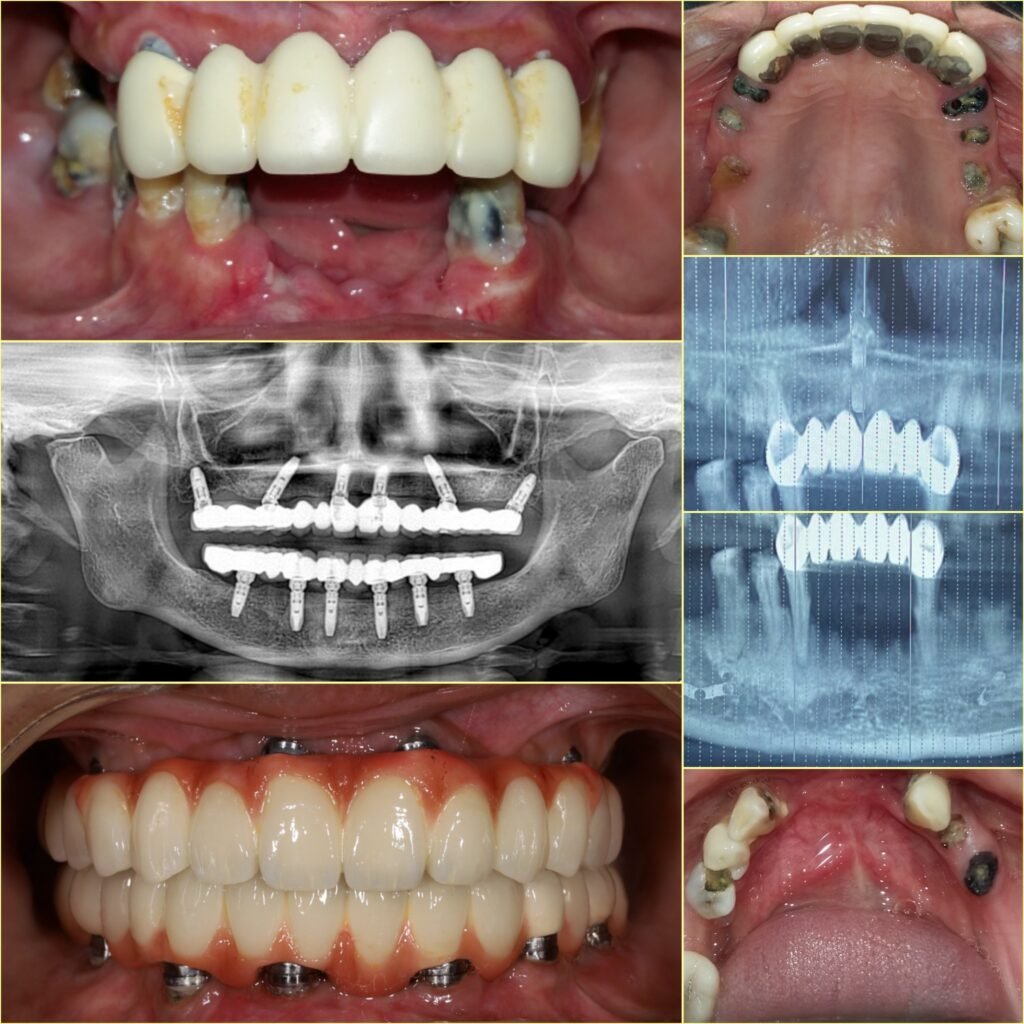

Dental implants are titanium posts placed into the jawbone to replace missing tooth roots. Once the implant integrates with the bone, it supports a custom-made crown, bridge, or denture that looks and functions like a natural tooth.

11. Advanced Technology for Precision

Modern implant procedures use digital imaging, CBCT scans, and guided surgery. The best dentist for dental implants in Rayasandra uses advanced tools to ensure accuracy and safety.

The Dental Implant Process: Step by Step

Consultation and Evaluation

The dentist examines your oral health using digital scans and X-rays.

Treatment Planning

A customized plan is created for precise implant placement.

Implant Placement

The titanium implant is placed into the jawbone under anesthesia.

Healing Phase

The implant fuses with the bone over a few months.

Crown Placement

A natural-looking crown is attached to complete the restoration.

Patients who choose the best dentist for dental implants in Rayasandra benefit from a smooth and well-planned process.